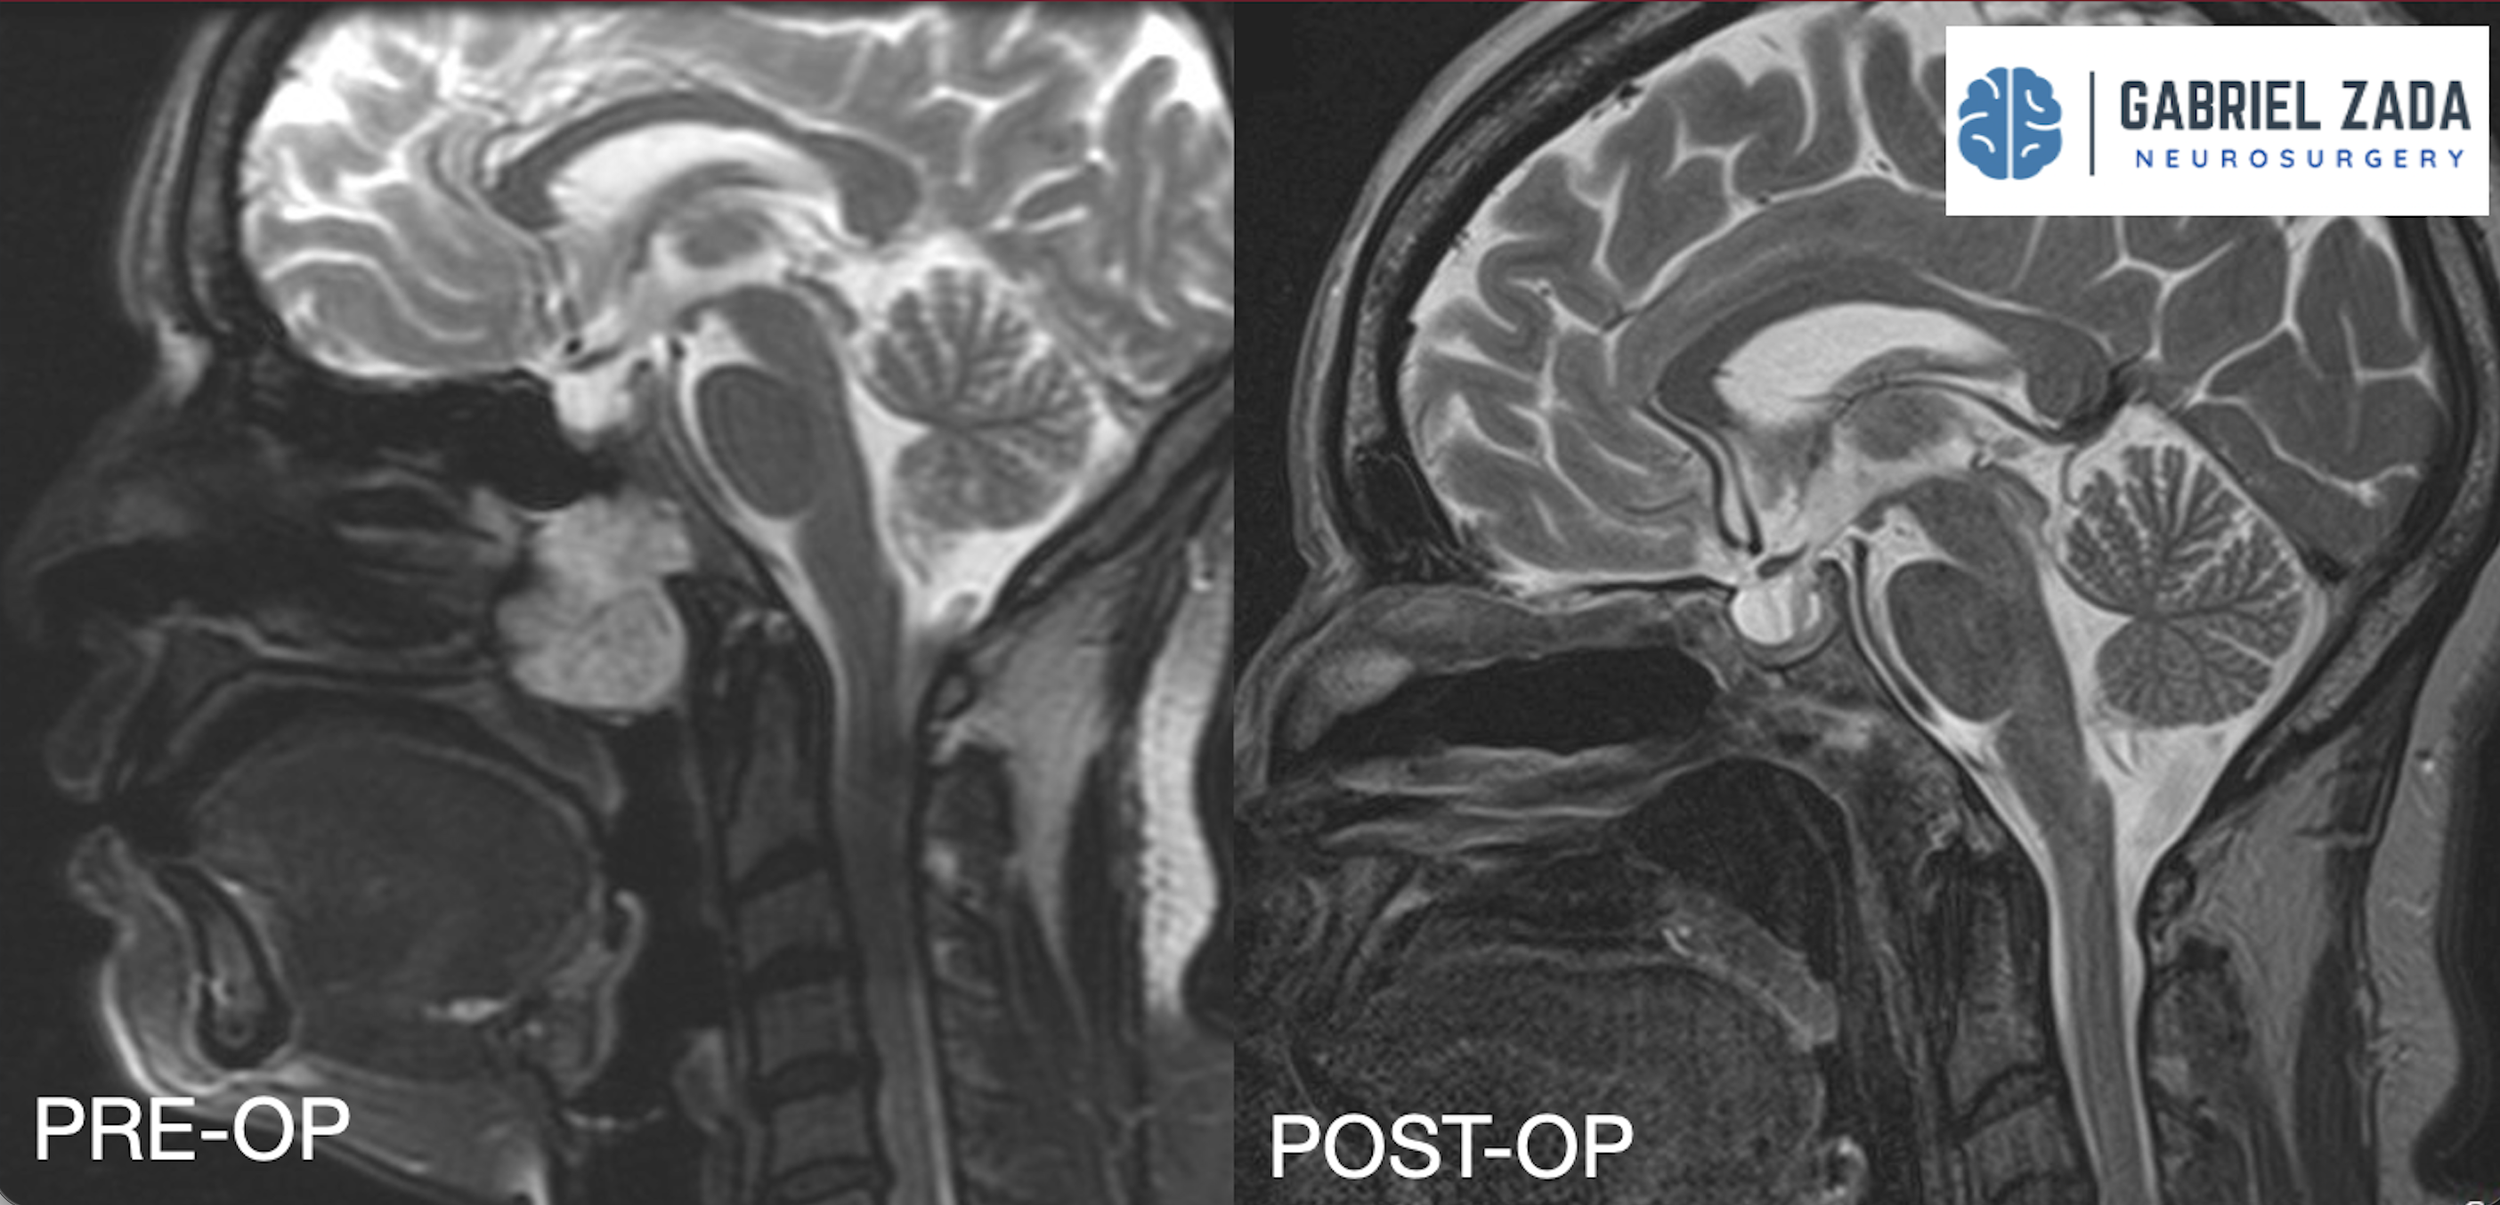

Explore this comprehensive gallery featuring pre‑ and post‑operative imaging of patients with skull‑base tumors treated by Gabriel Zada, MD, MS, FAANS, FACS. These cases highlight Dr. Zada’s expertise in advanced neurosurgical techniques and outcomes.

*Representative cases shown for educational purposes. All images de-identified. Individual results vary.